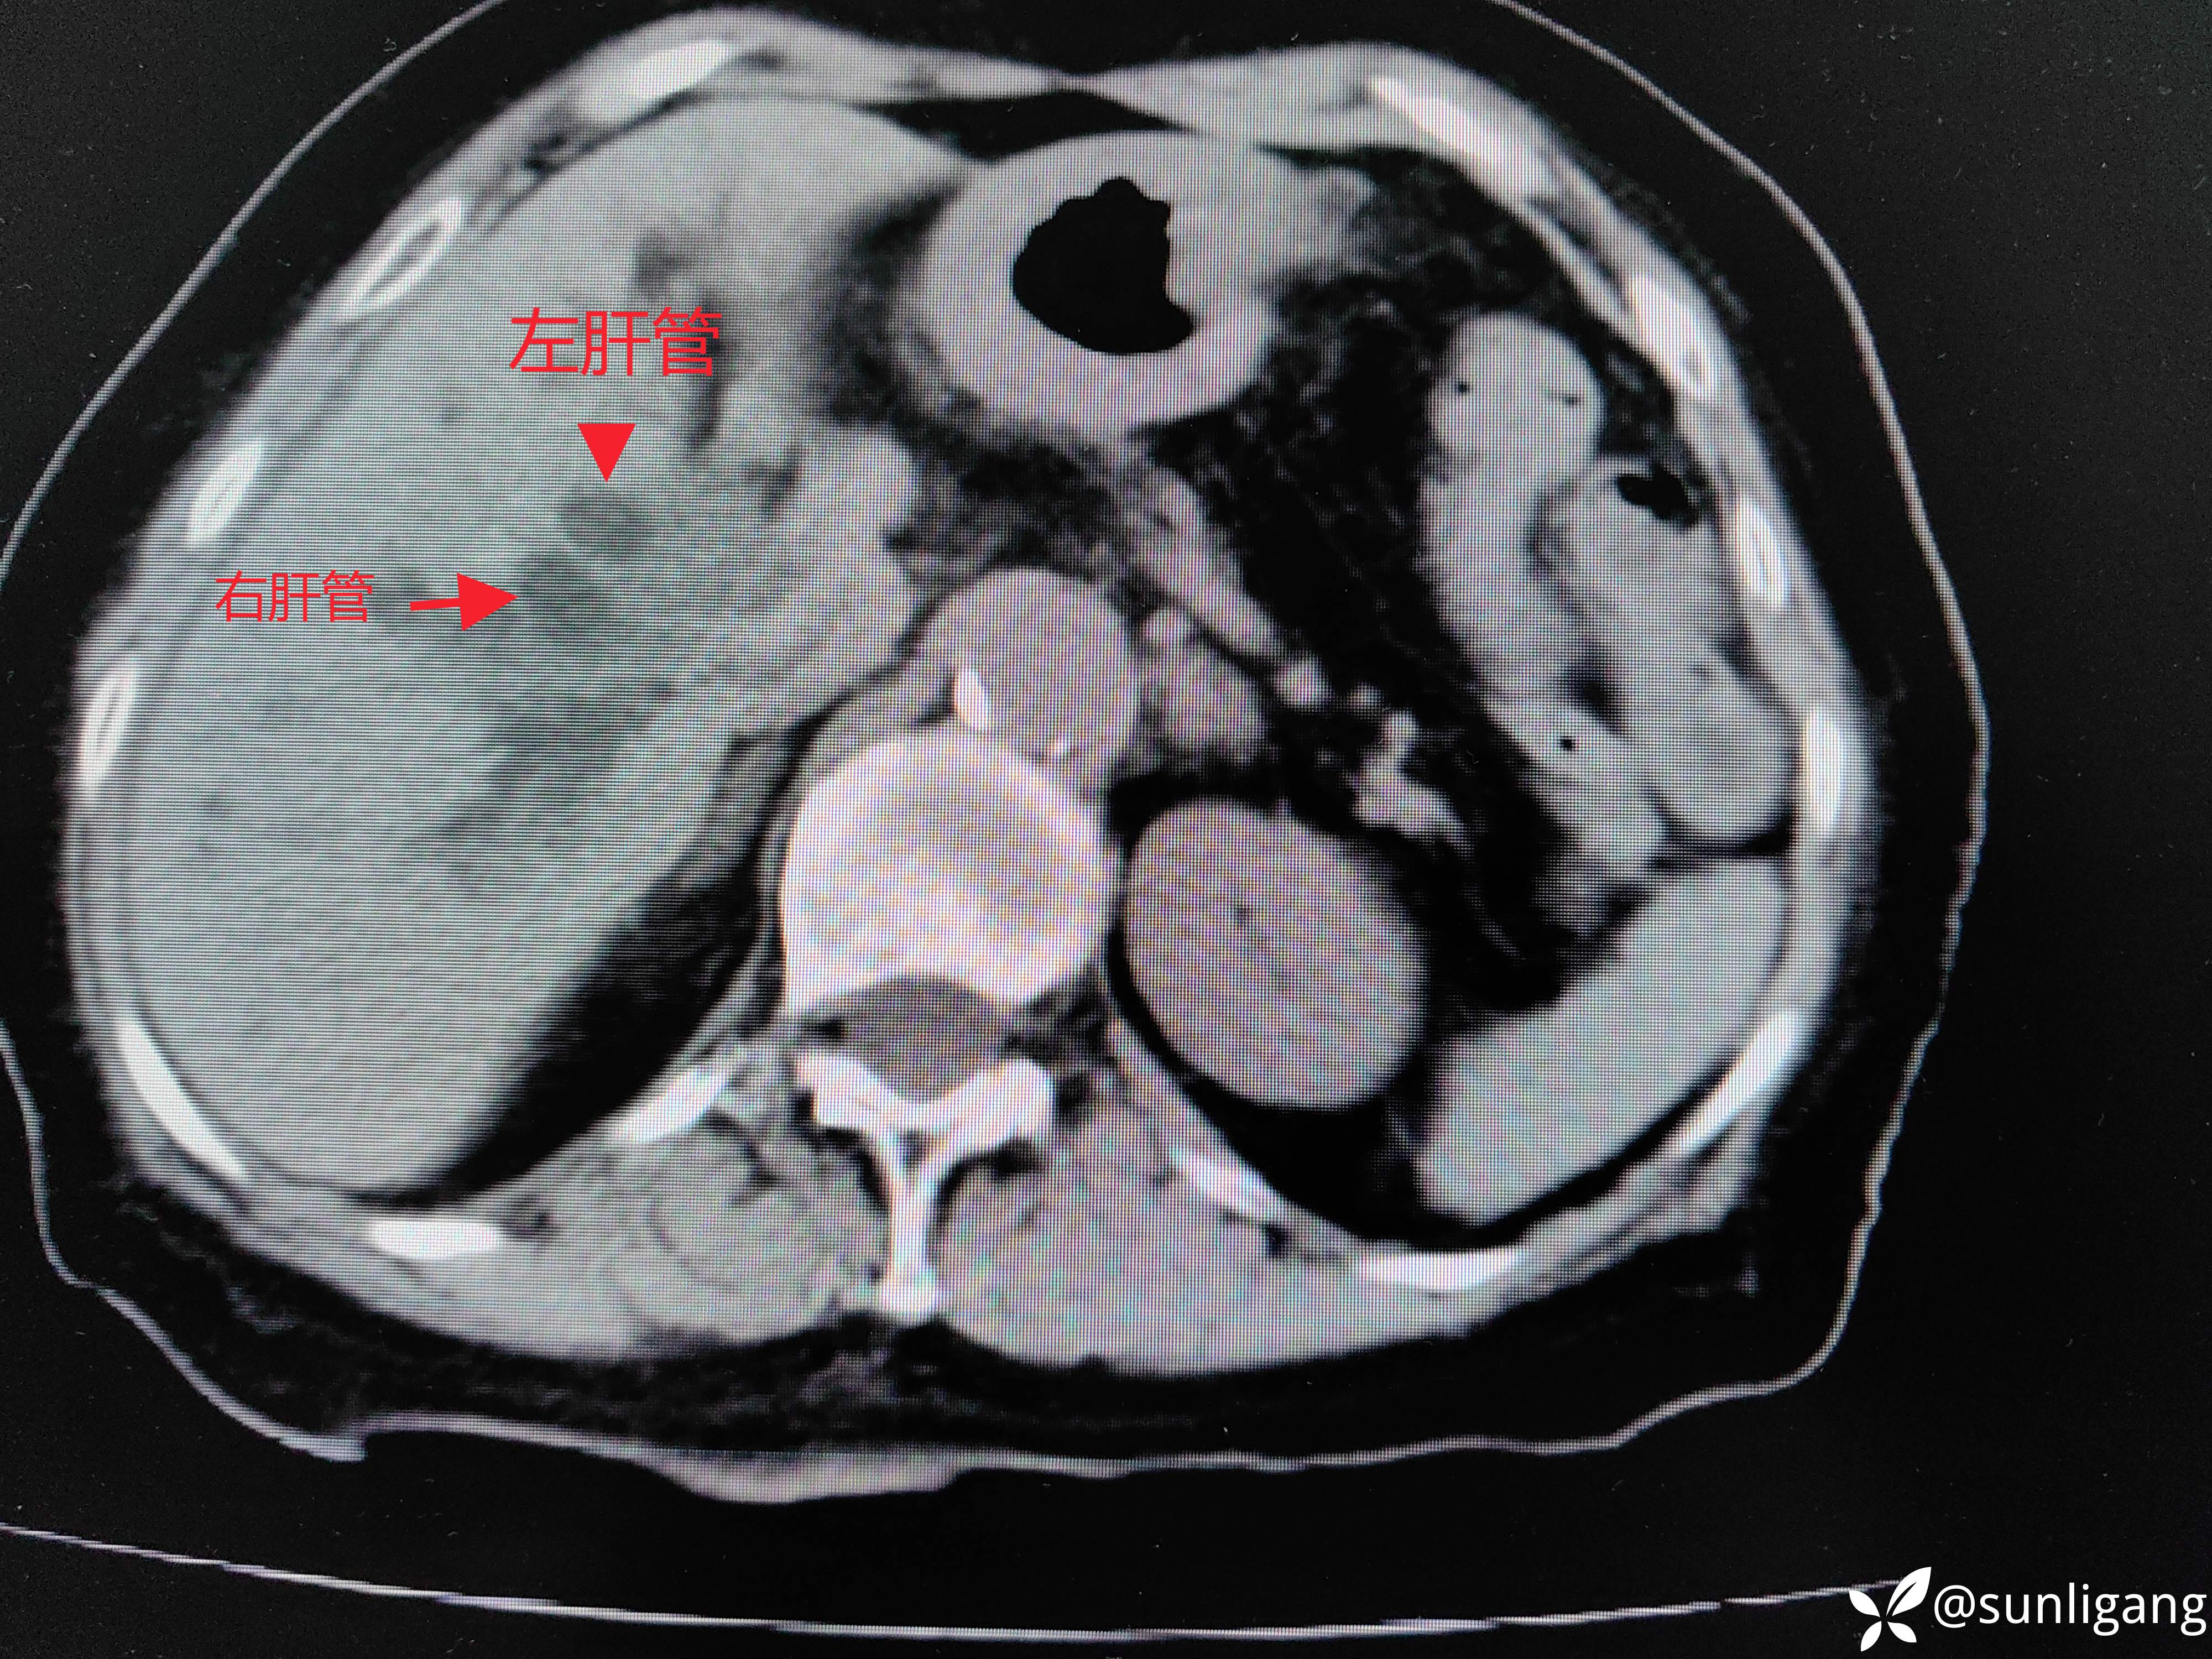

上腹部平扫+增强CT如下图:

左右肝管都有明显扩张